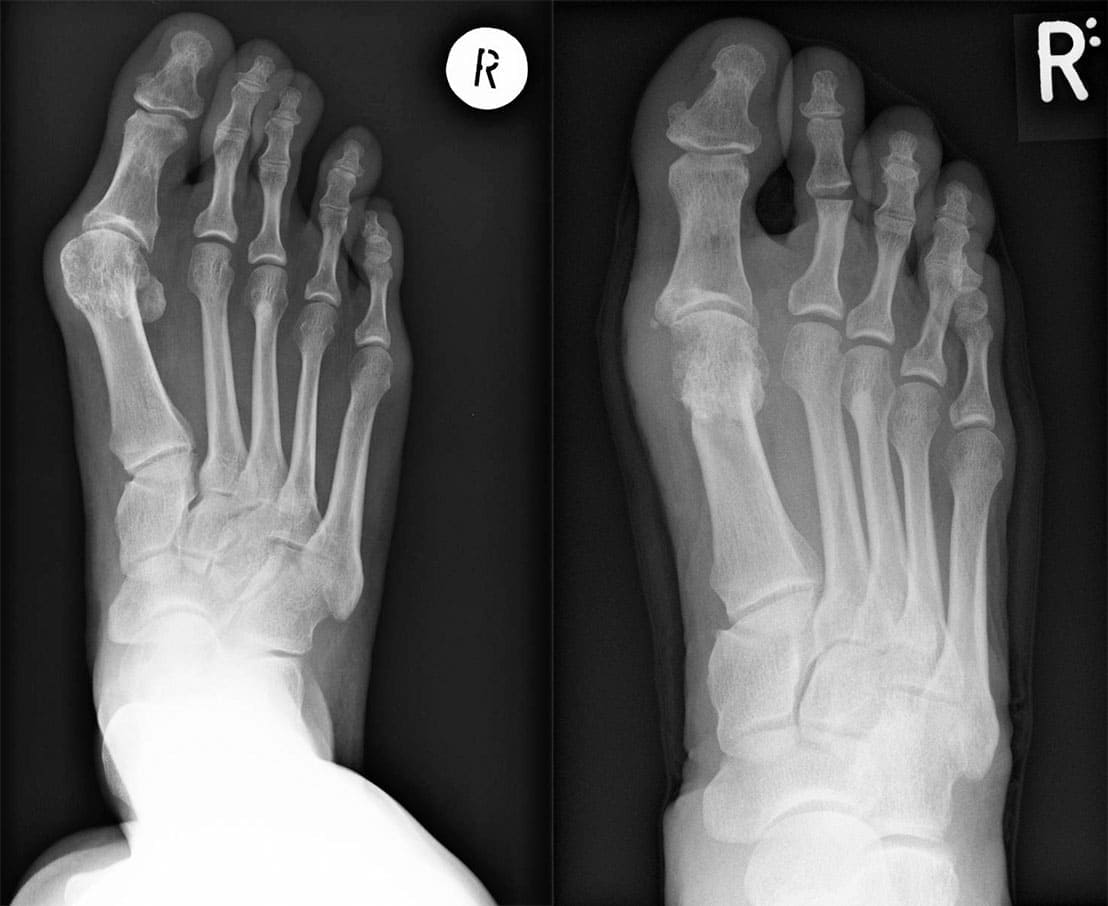

X-Ray Images: Before and After Treatment

It was devastating — but after reviewing my X-rays, the surgeon concluded that I needed urgent surgery to remove the bunion. The bone had already started causing complications in the surrounding joints, damaging ligaments, and putting me at risk of necrosis. If the tissue began to die, amputation could have been the only option. I was told that if I waited just a few more months, I might lose my entire foot. Necrosis is irreversible — once tissue dies, healing becomes extremely difficult. I was terrified. Naturally, I agreed to the surgery.If only I had known what I was signing up for…